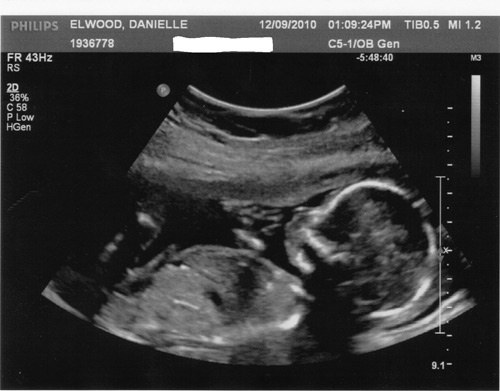

Rất nhiều mẹ bầu cầm tờ kết quả siêu âm thai trên tay nhưng không hiểu các chỉ số trong đó có ý nghĩa gì. Không ít mẹ lại chỉ quan tâm đến chiều dài, cân nặng của con, nhưng chị em cần biết rằng rất nhiều chỉ số khác cũng vô cùng quan trọng và mẹ nên biết những ký hiệu này.

Ký hiệu chỉ các thông số quan trọng của thai nhi:

CRL : crown rump length (chiều dài đầu mông)

BPD : biparietal diameter (đường kính lưỡng đỉnh)

TTD: Đường kính ngang bụng

APTD: Đường kính trước và sau bụng

AC : abdominal circumference (chu vi bụng)

FL : femur length (chiều dài xương đùi)

GS : gestational sac diameter (đường kính túi thai)

HC : head circumference (chu vi đầu)

AF : amniotic fluid (nước ối)

AFI : amniotic fluid index (chỉ số nước ối)

OFD : occipital frontal diameter (đường kính xương chẩm)

BD : binocular distance (khoảng cách hai mắt)

CER : cerebellum diameter (đường kính tiểu não)

THD : thoracic diameter (đường kính ngực)

TAD : transverse abdominal diameter (đường kính cơ hoành)

APAD : anteroposterior abdominal diameter (đường kính bụng từ trước tới sau)

FTA : fetal trunk cross-sectional area (thiết diện ngang thân thai)

HUM : humerus length (chiều dài xương cánh tay)

Ulna : ulna length (chiều dài xương khuỷu tay)

Tibia : tibia length (chiều dài xương ống chân)

Radius: Chiều dài xương quay

Fibular: Chiều dài xương mác

EFW : estimated fetal weight (khối lượng thai ước đoán)

GA : gestational age (tuổi thai)

EDD : estimated date of delivery (ngày sinh ước đoán)

Hiểu rõ những hý hiệu sẽ giúp mẹ “tự nghiên cứu” kết quả khám thai của mình.